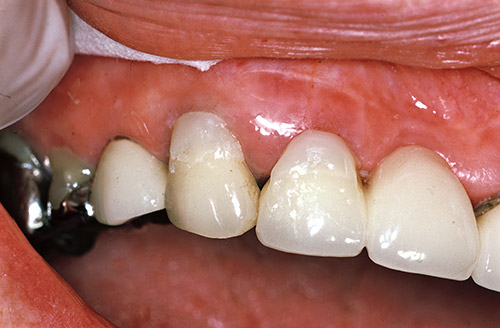

最初にクリアフィル トライエスボンドNDとクリアフィル マジェスティLVを用いた前歯部露出根面のう蝕の複数歯同時修復の実際について図1~11に示す。

1回のボンド採取で十分に3歯の修復が問題なく行われた。

図12~18に前歯部メタルボンド修復歯の歯頸部根面露出に伴う複数歯の補修修復の症例を示す。

本症例では、トライエスボンドNDとポーセレンボンドアクチベーターの混和物がボンディング材として用いられた。